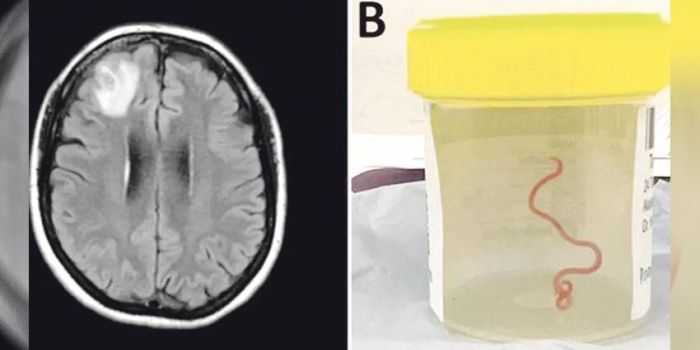

Ev kurmekî parazît bû, lê esas ew kurm hîç bi mirovan re peyda nabe. Ew kurmê parazît bi marên pîton re peyda dibe. Nexweşa 64 salî ji ber semptomên parazîtan Çileyê 2021´ê çûbû nexweşxaneyê. Lê sala 2022´yan li semptomên wê bîrokebûn û depresyon jî zêde bû. Piştî ku laşê wê bi MR´ê hat scankirin, kurm xuya bûye.

Kurmî ji pisporekî re dişînin û ew jî ecêbmayî dibêje, “Ev Ophidascaris roberts e.” Yanî bi vê bûyerê re, ev cara pêşî ye ku ev parazît li cem mirovan hatiye dîtin. Ji ber ku jina 64 salî nêzî golekê giya û pincar kom dikirin û li wir pîton jî gelek in, li gorî texmînan vî kurmê parazît ji van pincar û gihayan vegirtiye wê.